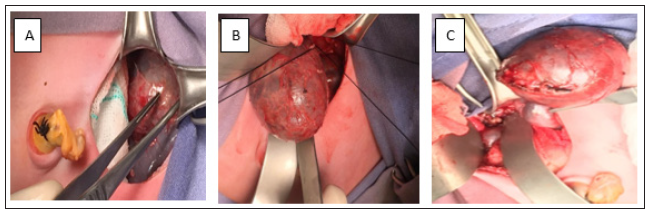

Undergo surgery; a left Middle line incision of the abdomen was performed to identify the tumor in the superior pole of the left kidney, after dissecting and moving the left colon and splenic angle of the colon. The tumor was localized and its nutritional veins were ligating from the suprarenal artery and vein. Hence, under careful ramous dissected the tumor was dislocated and exposed enough between the superior pole of the left kidney and adrenal gland from the lumbar column. Satincky clamp was placed to the part inferior of the tumor that permits the extraction of the tumor and biopsy of the suprarenal gland (Figure 3). Vein and artery of the tumor were sutured with the 6/0 PDS. Pathologic examination reveals stage 1 of neuroblastoma (Figure 4).

Figure 3: Congenital cystic and solid components of neuroblastoma: A. Image shows left incision and intestinal displacement with ischemic. B. Image demonstrates dislocation of the tumor and C. Image shows total extraction of the tumor.